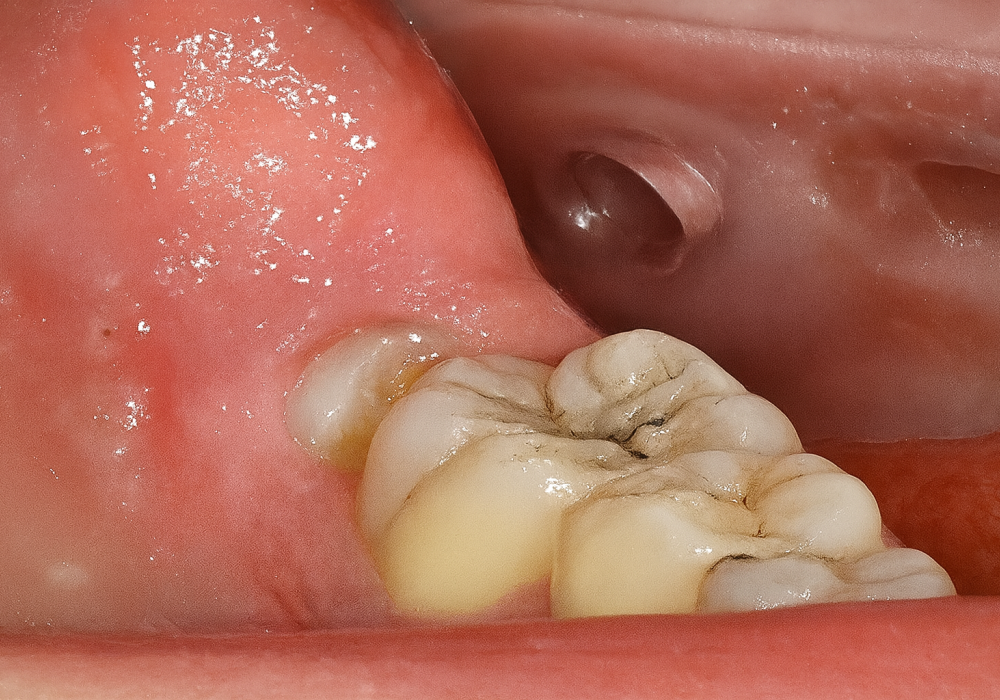

Colocación de implante postextracción con provisionalización inmediata en el sector estético: caso clínico con seguimiento a 4 años